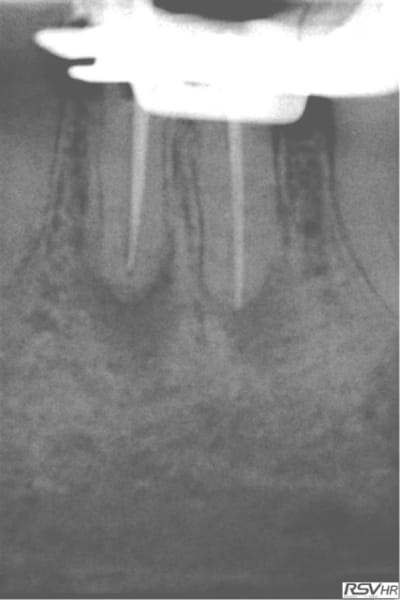

Voici un exemple de couplage microscope opératoire/cbct

RTE 36 en octobre2012 ;3 heures de RTE pour recherche de canaux sous micro inserts ultrasons/il y avait une LIPOE

digue+hypo+système R-endo microméga instruments à mains

vérification au CBCT en 2016

disparition des LIPOE

ici on obtient une guérison apicale